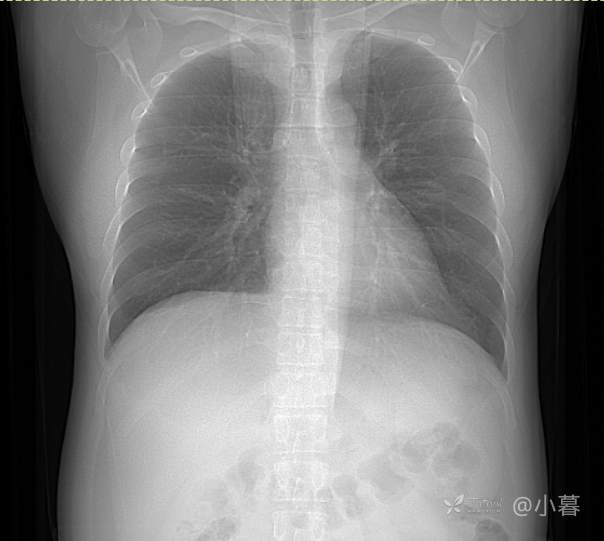

双肾超声无异常,无浆膜腔积液,体型尚正常,无腹型肥胖,轻度脂肪肝